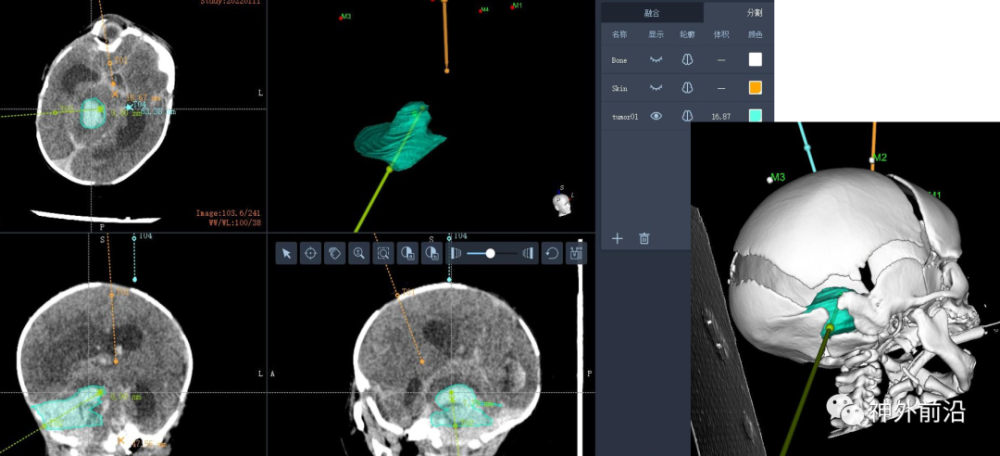

黄礼德:本病例我们做了两个手术计划,也就是两个穿刺路径,其中一个是穿刺血肿,另一个是引脑脊液。

术后我们做了验证,第一个手术路径跟手术计划完全吻合;第二个手术路径稍有偏移,因为这新生儿头颅是术中医生双手固定,在穿刺过程会存在偏移的可能,不像成年人或者大龄的儿童能够头架固定头部。本例病例术中患者注册精度0.21mm,机械臂注册精度0.09mm,精度非常理想,完全可以满足我们手术需求,术后手术路径验证也是完全吻合。

辅助检查:头部CT:两侧小脑半球出血并破入脑室,继发脑室积水。出血量约17ml。

4.手术规划